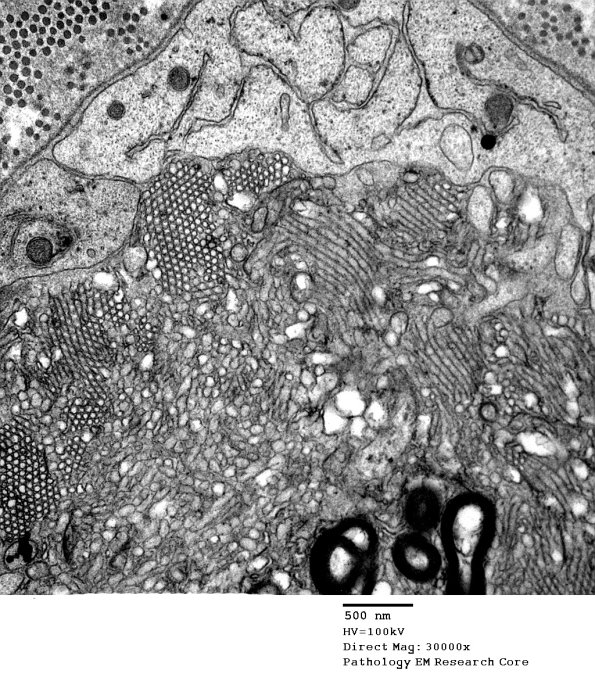

Washington University Experience | PERIPHERAL NEUROPATHY | 4 AXONAL DEGENERATION | 3 Electron Microscopy | 2G5 Axonal Degeneration (Case 7) EM 020A - Copy

In this region there are vesicular myelin changes and adjacent Schwann cell processes which may resemble axons. Ribosomes in Schwann cell processes often give a hint they are not axons.